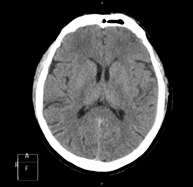

- Neurorradiología- TC Cráneo Prueba radiológica que consiste en obtener imágenes del cráneo de alta definición anatómica (tronco cerebral, cerebelo, cerebro, calota craneal, etc.), mediante el empleo de un equipo de TC (Tomografía Computarizada).Indicaciones: traumatismos, cefalea, trastornos de la memoria, pérdida de fuerza súbita en una extremidad o mitad del cuerpo. Prueba radiológica que consiste en obtener imágenes del cráneo de alta definición anatómica (tronco cerebral, cerebelo, cerebro, calota craneal, etc.), mediante el empleo de un equipo de TC (Tomografía Computarizada).Indicaciones: traumatismos, cefalea, trastornos de la memoria, pérdida de fuerza súbita en una extremidad o mitad del cuerpo.